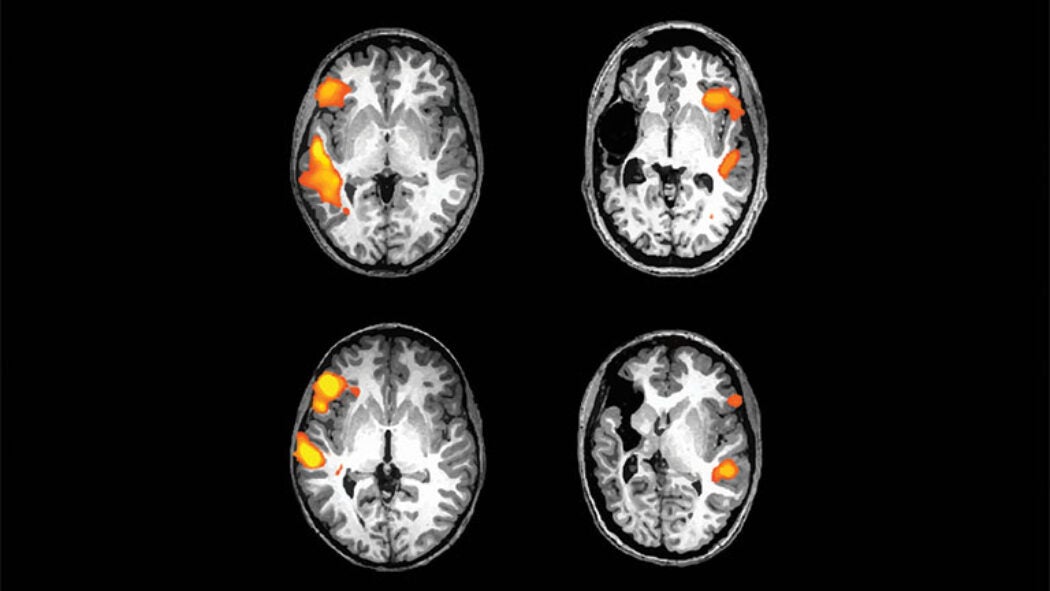

Connecting the Dots: Dyslexia and Math

Why are children with dyslexia more likely to also struggle with dyscalculia—the understanding and manipulation of numbers?